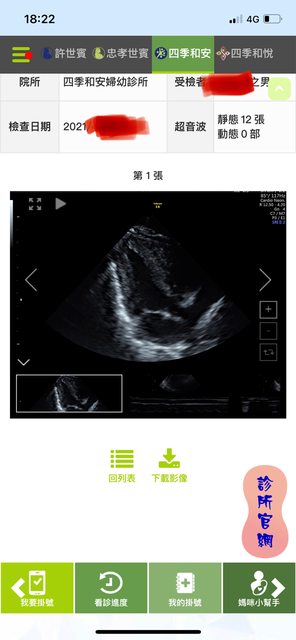

我有印象這篇文 那你要說文字很像我也沒話說 還是我拿三胎的超音波照給你? 第一胎在台北生的 二三胎後來都在禾馨看 https://i.imgur.com/Ohujwd9.jpg